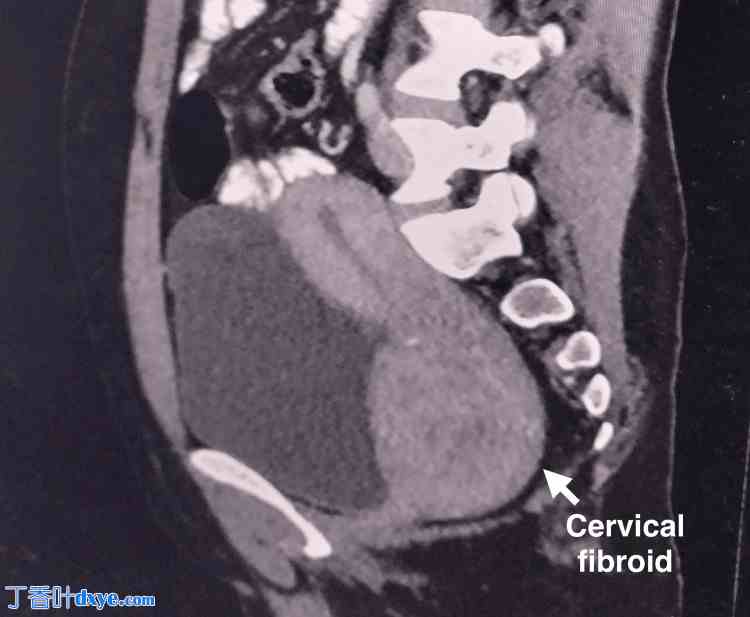

一名35岁、既往有正常分娩史(孕1产1)的女性,因月经过多就诊于院。她无任何压迫症状。腹部柔软,无压痛,未触及腹盆腔肿块。阴道窥器检查发现宫颈前唇增厚,宫颈后唇变薄并覆盖于肿块之上。双合诊检查发现宫颈前部触及一8×7 cm肿块,向上延伸至子宫体部,上缘未触及。超声检查显示子宫前倾,子宫内膜厚度为7.5 mm。如图1所示,在子宫体下部和宫颈处发现一边界清晰的异质回声病灶,大小为6.7 x 7.4 x 7.2 cm(约180 cc),可能为子宫肌瘤。

图1. 超声图像显示子宫体下部和宫颈处有一边界清晰的异质回声病灶,大小为6.7 x 7.4 x 7.2 cm(约180 cc),可能为较大的宫颈肌瘤。